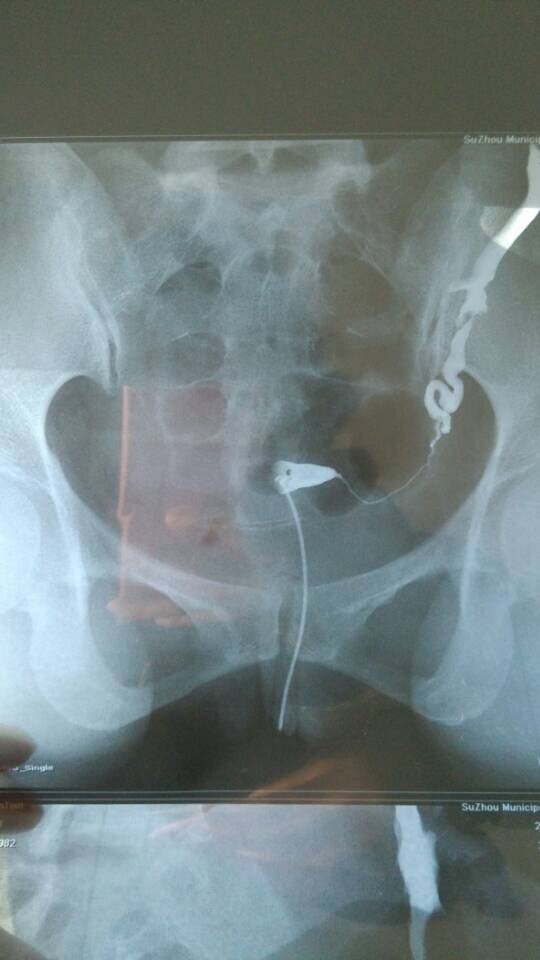

输卵管造影显示一侧不通,做宫腹腔镜成功率多大? 结婚一年未孕,14年10月份做了输卵管造影,显示右侧不通,所以医生建议做宫腹腔镜,但是我在网上查到说这个手术不是所有的都能疏通,而且要全身麻醉,副作用较大,还会感染炎症,我本身有霉菌性阴道炎,且在11年有做过一次人流,想请哪位专家帮我看看我这个情况做这个手术右侧疏通的几率多大、这个手术真的成功率很低吗?我该怎么办?而且连续两个月堵的那一侧在排卵,我可不可以打促排卵的药促使两边都排卵?还有输卵管上举做人工是不是会宫外孕啊??问题很多,多谢各位专家了 点击展开 匿名用户 2015-01-04 15:14 推荐回答 你好,做腹豆柴腔镜手术比较好一点,让自己自然怀孕比较好,做人工受精成功率也不是很高的而涌渐神且畸形率比较唉究大。 cn#BfuaaGVkLG 2015-01-05 14:58 宝宝知道提示您:回答为网友贡献,仅供参考。 相关问题 输卵管近端堵塞;用宫腹腔镜手术成功率多少?求专家指点都快离婚了因为不孕 输卵管造影多久可以做宫腹腔镜 输卵管不通做了宫腹腔镜手术已经快一年了,还未孕,还用再做造影检查吗

结婚一年未孕,14年10月份做了输卵管造影,显示右侧不通,所以医生建议做宫腹腔镜,但是我在网上查到说这个手术不是所有的都能疏通,而且要全身麻醉,副作用较大,还会感染炎症,我本身有霉菌性阴道炎,且在11年有做过一次人流,想请哪位专家帮我看看我这个情况做这个手术右侧疏通的几率多大、这个手术真的成功率很低吗?我该怎么办?而且连续两个月堵的那一侧在排卵,我可不可以打促排卵的药促使两边都排卵?还有输卵管上举做人工是不是会宫外孕啊??问题很多,多谢各位专家了